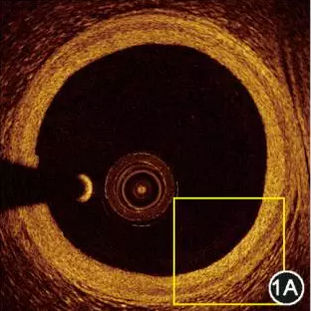

一文详解:冠状动脉扩张的诊治

在冠状动脉造影中,常常会遇到一种特殊的病变,即冠状动脉扩张。其发病机制和冠状动脉狭窄相近,但又不完全相同,在治疗策略上也有一些独特之处。下面我们就来认识一下冠状动脉扩张.临床研究